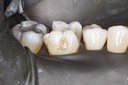

Wayne Chin #2 pre-op

Wayne Chin #2 prep

Wayne Chin #2 finish